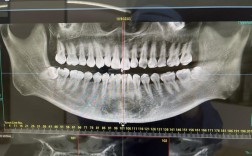

技术创新是周彦恒教授在论坛中反复强调的核心议题,随着数字化技术的发展,传统正畸诊断与治疗模式正经历深刻变革,他系统介绍了口内扫描、CBCT影像分析、3D打印模型等技术在诊断设计中的应用,提出“虚拟矫正方案”概念,通过模拟牙齿移动路径、预测治疗效果,显著提高了矫治精准度与患者满意度,尤其在隐形矫治领域,他针对常见问题如附件设计、牙根控制、复发预防等,分享了团队总结的临床经验,并通过大量病例对比分析,论证了数字化技术对缩短治疗周期、降低并发症风险的积极作用,以下为周彦恒教授主要学术研究方向与成果概览:

| 数字化正畸 | 建立基于AI的错颌畸形分类诊断系统,开发个性化矫治方案设计软件 | 提升诊断效率,实现矫治过程的可视化与精准化 |